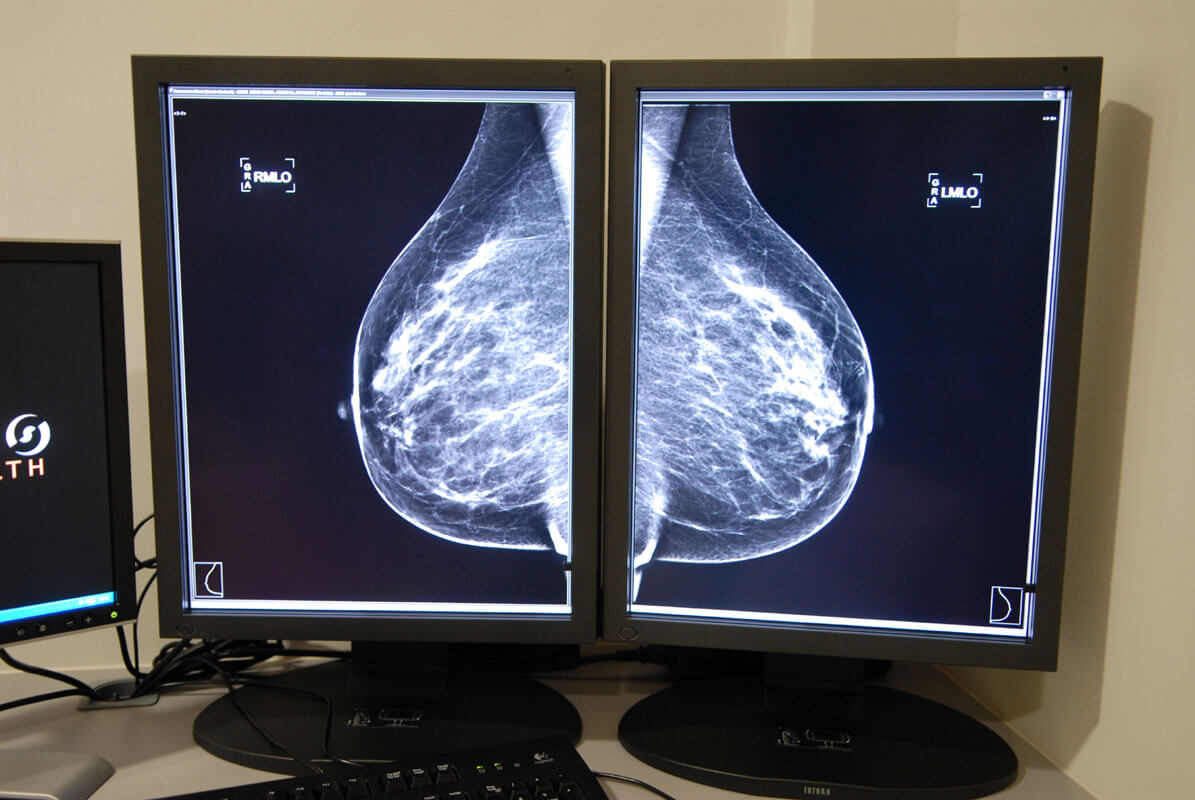

Según publica este miércoles el digital OKDIARIO, el Gobierno de Emiliano García-Page reconoce en el nuevo contrato del servicio de mamografías para el área sanitaria de Talavera de la Reina (Toledo) que la «población diana» son 12.000 mujeres, por lo que el Ejecutivo socialista dejó sin mandar la carta a cerca de 8.000 pacientes a raíz del cierre repentino del centro concertado el pasado mayo. Es decir, la Junta no mandó en tiempo y forma seis de cada diez cartas previstas para el ejercicio de 2025.

Ahora, el nuevo contrato licitado por la Junta para esta zona sanitaria cifra en 12.000 la «población diana». «La estimación de mujeres (entre 45 y 70 años) en Castilla-La Mancha que aceptan participar y realizarse el examen mamográfico se realiza con la proyección basada en la participación registrada en las campañas anteriores en la aplicación informática de gestión del programa, que aplicada a la población diana anual objeto de examen, concluye una estimación de exámenes a realizar de 12.000 cada año, aproximadamente», señala la Consejería de Sanidad en el expediente consultado por este periódico.

De esta forma, teniendo en cuenta que entre enero y finales mayo se hicieron 4.407 mamografías de mujeres ya citadas, y que trabajadores del propio centro concertado han admitido que dejaron de llamar a las pacientes en abril, son cerca de 8.000 las citaciones que se quedaron sin efectuar.